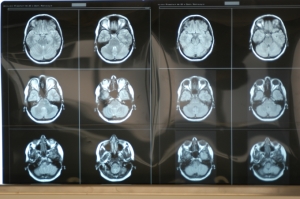

Anatomie und Schnittbilddiagnostik im Präpariersaal: